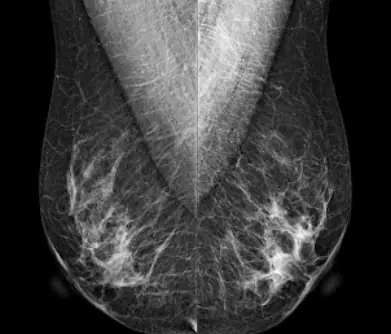

La mamografía digital 2D obtiene imágenes planas de la mama comprimida desde dos proyecciones estándar: cráneo-caudal (CC) y medio-lateral oblicua (MLO). Estas imágenes representan una suma de todo el tejido mamario en un solo plano. En contraste, la tomosíntesis realiza múltiples adquisiciones durante un movimiento en arco del tubo de rayos X, que generalmente oscila entre 15 y 50 grados.

Estas imágenes individuales, tomadas desde distintos ángulos, son procesadas mediante algoritmos avanzados que reconstruyen cortes delgados del tejido, con un grosor de 1 mm, lo que permite visualizar la mama en forma tridimensional.

En la mamografía 2D, las estructuras anatómicas se superponen en una única imagen, lo cual puede ocultar lesiones pequeñas o simular hallazgos patológicos. La tomosíntesis, al ofrecer cortes secuenciales, permite evaluar el tejido capa por capa. Esta visualización tridimensional proporciona un mayor contexto anatómico y facilita una diferenciación más clara entre tejido normal y alteraciones sospechosas.